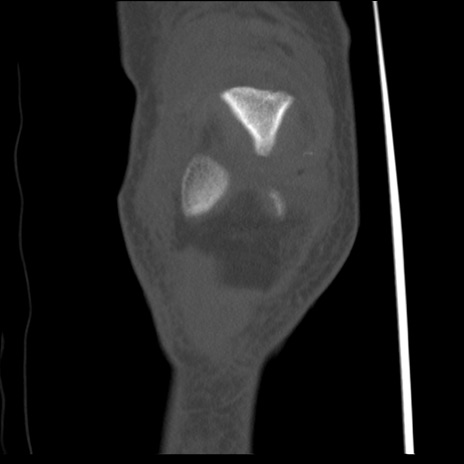

右膝関節CT

横断像